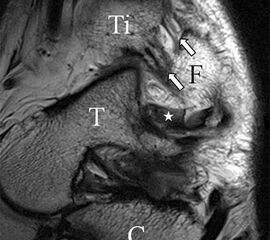

Die Kombination aus 3 Tesla Hochfeldtechnik und/oder Verwendung hochauflösender Spulen (Empfangseinheiten des Signals) erhöht die Signalausbeute. Dies erlaubt mit akzeptablen Messzeiten (3-4 Minuten pro Sequenz) im Routinebetrieb eine Darstellung mit einer Schichtdicke von 1-2 mm und einer Ortsauflösung von 0,2 x 0,2 mm in der Schichtebene in den anatomisch am besten zeichnenden 2D Turbospinechosequenzen. Der Unterschied der diagnostischen Wertigkeit zwischen einer kernspintomographischen „Standarduntersuchung“ und einer HR-MRT wird besonders in der chondralen Diagnostik sichtbar (Abb. 1 a-c). Unter Verwendung von 3D Sequenzen, die jedoch entscheidende Schwächen bei der Darstellung der Ligamente aufweisen, werden sogar Schichtdicken weit im Submillimeterbreich erreicht. Eine weitere Erörterung der Sequenz spezifischen Eigenheiten soll jedoch an dieser Stelle unterbleiben.

Das Ligamentum fibulotalare anterius entspricht einer bifaszikulären Struktur (Abb. 2 a) mit interponierendem fibrovaskulärem Gewebe (S. K. Sarrafian (ed). 2003). Es gibt jedoch Variationen der Ligamentanatomie. In 55% liegt das LFTA als bifaszikuläres Band (Abb. 2 a), in 9% als monofaszikuläre Bandstruktur (Abb. 2 b) und in 36% als multifaszikuläre, striäre Variante (Abb. 2 c) vor 3.

Das LFTA verbindet die antero-inferiore Fibulaspitze mit dem Processus lateralis tali und inseriert hier an einem oder zwei kleinen Tuberkeln 3. Der in Neutralposition horizontale Verlauf erleichtert die kernspintomographische Darstellung in dieser Standardebene. Das LFTA weist durchschnittlich eine Breite von knapp über 2 mm auf 4. Somit sind bei einer Routinedarstellung in 3 mm Schichtdicke Anschnittsphänomene, die die Diagnostik erschweren, regelmäßig anzutreffen. Dementsprechend sind auch die ligamentären Subfaszikel nicht zu differenzieren. In koronarer Darstellung ist dies aufgrund der hohen Auflösung in der Schichtebene jedoch möglich (Abb. 2 a-c), wobei hier wiederum eine Integritätsbeurteilung des Bandes erschwert ist. Unter Verwendung hochauflösender Techniken im Millimeterbereich (Schichtdicke) sind hingegen auch in der axialen Ebene die subfaszikulären Strukturen zu beurteilen (Abb. 3).